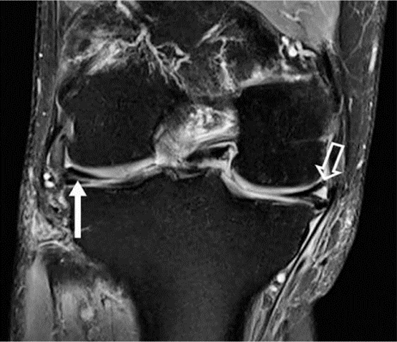

Hình 7. Vết rách ngang sụn. Hình ảnh pd coronal xóa mỡ với tín hiệu tuyến tính trong sụn (mũi tên đóng) kéo dài đến mặt dưới của thân sụn bên, phù hợp với vết rách. Tín hiệu cao (mũi tên mở) ở mặt ngoài, mặt sụn giữa không kéo dài đến bề mặt tạo hình sụn và phù hợp với thoái hóa niêm mạc.